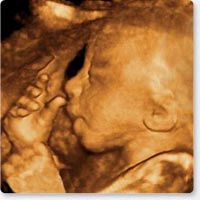

Live 3/4 D Ultraschall

12. SSW